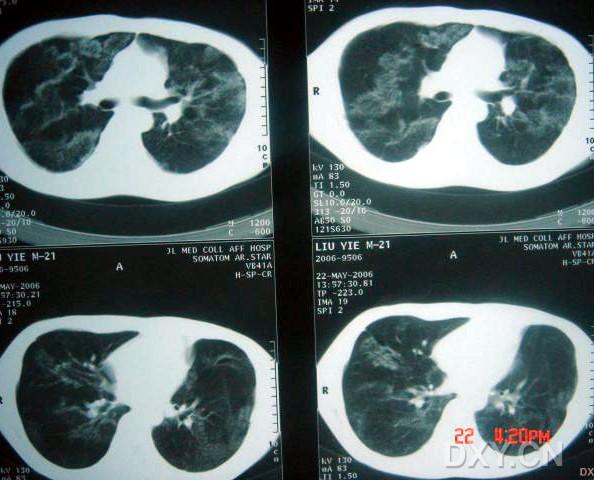

影像表現(xiàn):

兩肺彌漫性顆粒狀陰影,部分陰影融合呈團塊狀,可見支氣管氣相;

呈非對稱,非均勻分布性,部分肺野呈磨玻璃密度;

多處胸膜局限性增厚,胸水征(--)縱隔窗為正常。